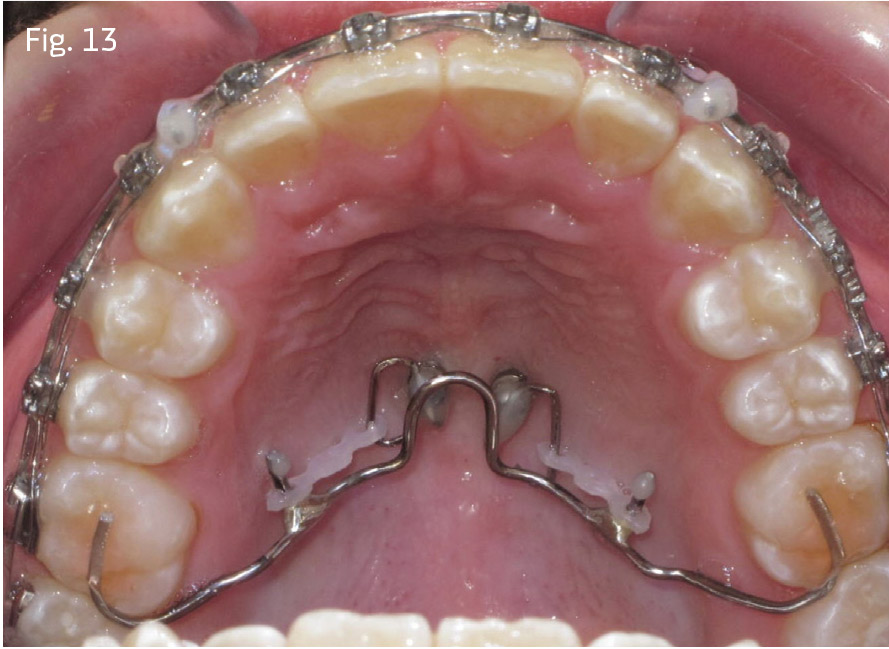

In both cases, passive self-ligating brackets with standard anterior torque prescription were placed. Quarter-inch, 2-ounce posterior cross-elastics were used as needed from the lingual of the upper molars to the labial of the lower molars from the first archwire insertion of .014 copper nickel titanium (CuNiTi). The archwire sequence of 14x25 unit, 18x25 CuNiTi, 19x25 stainless steel was followed with 10-week appointment intervals. The posterior crossbite relationships in Case 1 were corrected before advancement to 18x25 CuNiTi. In Case 1, once both arches were worked to 19x25 stainless steel, a Rocky Mountain Orthodontics fixed/removable transpalatal arch was inserted into the vertical lingual sheaths of the upper molar bands, with 6mm of clearance relative to the palate (Fig. 12). In Case 2, molar bands were avoided by placing a bonded TPA bent from .036 stainless steel. It was bonded to the occlusal surfaces of the upper first molars (see Fig. 13). This prevents lingual rolling of the buccal segments during intrusion.

In Case 2, two 6mm miniscrews were inserted at the paramedian locations shown to be reliable in the CBCT simulation, and half-dumbbells were bonded into the cross-slots of the heads of the miniscrews. Lingual buttons were bonded to the second bicuspids and first and second molars; 75g of individual elastic chain force was applied from the dumbbell attachments to the molars and second premolars in both cases.